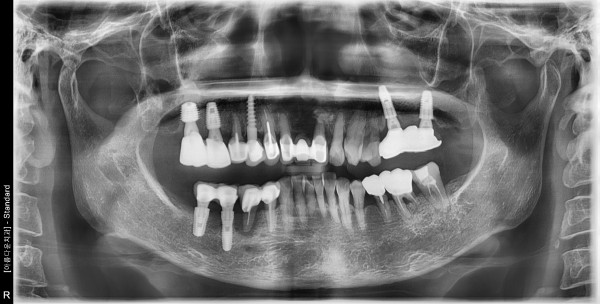

64세 여자 상하악소구치 발치,치조골이식,임플란트 식립